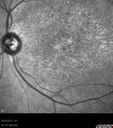

36-year-old man was seen by me in the office on August 23, 2012. I started seeing him years ago. His father in fact is an ophthalmologist. He started to notice vision change sometime in his early twenties. He has had progressing macular atrophy and unfortunately has poor vision in the left eye. The right eye continues to see decently. VISUAL ACUITY: OD 20/40, OS 20/200. IOP: OD 10, OS 12. The lenses are clear. EXTENDED OPHTHALMOSCOPY: OD: Vertical C/D ratio is 0.3. The macula looks atrophic. OS: Vertical C/D ratio is 0.3. The macula looks atrophic. The retinal vessels are fine. FUNDUS PHOTOGRAPHY - INFRA RED: The image shows hypopigmentation centrally. SPECTRALIS-SD-OCT SCAN: The OCT scan shows retinal atrophy in the center of both eyes with loss of the outer retinal layers. The choroid looks unusual in him, almost like the choriocapillaris is thinned out and the large choroidal vessels are more abundant. FUNDUS PHOTOGRAPHY - AUTO FLUORESCENCE: The image shows a ring of hyper auto fluorescence in the posterior pole within the macular arcades, which is a linear bright ring. Inside of that there is some hypo auto fluorescence, but not terribly so and he does seem to have decreased macular pigment in both eyes. IMPRESSION: 1. PROBABLE CONE DYSTROPHY – BOTH EYES AUTOSOMAL RECESSIVE DISCUSSION: I explained to the patient now that genetic testing is available, I think it would be best to characterize his dystrophy toward the goal of having genetic testing done and then ultimately and possibly, if it becomes available, offering him some sort of treatment.

dystcone_chsa_082313_06.jpg

Macular possible Cone Dystrophy - Infra-red628 views00000